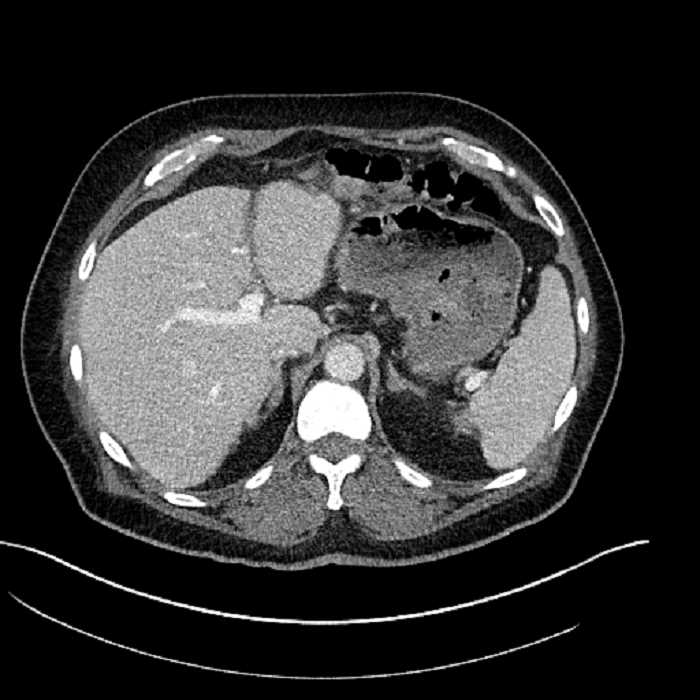

• Large fluid density structure in hepatic segments 7 and 8 measuring 10 x 7 x 7 cm with internal septation and circumferential ill-defined low density compatible with edema

• Peripherally enhancing subcapsular collections along the anterior margin of the left hepatic lobe measuring 3 x 1 cm and 2 x 1 cm

• Clearly marginated fluid density structure in segment 7 and several other scattered tiny hypodensities, which likely represent cysts

Acute sigmoid diverticulitis complicated by a small contained perforation and a large abscess in the right hepatic lobe. Additional small subcapsular abscesses along the anterior margin of the left hepatic lobe.

• The classic CT imaging appearance is a double target sign with internal low density surrounded by an internal enhancing rim (capsule) and a low density external rim (edema)

Hepatic abscess showing the double target sign with low density internally surrounded by a thin inner enhancing rim (red arrow) and ill-defined outer low density rim (yellow arrow). Blue arrow indicates an internal septation. Red arrows: additional smaller subcapsular abscesses. Red arrow: focal contained perforation associated with diverticulitis.